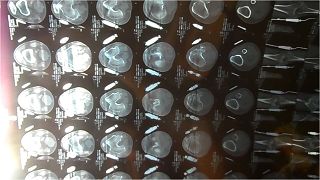

治疗期间的CT截图

他被送到市医院抢救,刚送进医院的时候他不省人事、胡言乱语,到了后半夜就能认人了,也不说胡话了。经检查他左腿膝盖骨撞碎,筋也断了。

在他住院一个多月后,他说老感觉头沉,经过做脑CT才发现他头渗血,医生才给他固定,不让动了,并说动的话会出现危险。可是此前的一个月,他经常动,还拄着拐外出也没出现任何危险,这就是受大法的保护才出现的奇迹。